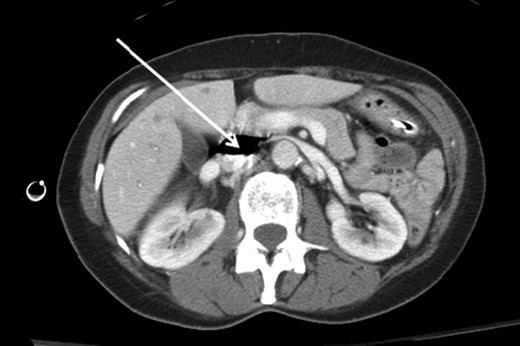

A 66-year-old female patient presented to our level I trauma center after a motor vehicle collision. She sustained multiple injuries including several fractured ribs, hemopneumothorax and a right diaphragmatic rupture. She was hemodynamically normal during her primary and secondary survey, and received a right femoral vein central venous catheter (CVC) for fluid resuscitation. She underwent computed tomography (CT) scan for further diagnostic evaluation and was noted to have the aforementioned injuries and a significant amount of air within the IVC, right iliac and femoral veins (Figs. 1–3). She was immediately placed in Trendelenburg position; a new subclavian CVC was inserted and used to withdraw air. Her right femoral vein introducer was suspected to be the source and was removed. She remained stable with no obvious clinical sequelae and underwent operative repair of her diaphragmatic injury. The patient was discharged on hospital Day 10 with no issues.

Coronal CT image of the abdomen and pelvis showing a significant amount of air within the IVC (white arrow). Note the CVC (blue arrow) and additional air (red arrow) in the right external iliac vein.